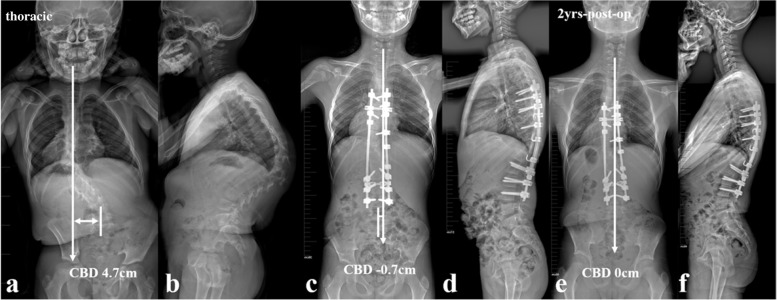

All the recruited patients were stratified according to the location of dystrophic curve apex: thoracic group, 4 cases (26.7%) (Fig. 1a, b); thoracolumbar/lumbar group, 11 cases (73.3%) (Fig. 1c, d). Among them, 1 patient in thoracic group and 3 patients in thoracolumbar/lumbar group received staged surgery with combined posterior-anterior or anterior- posterior approach (Table 1), while the rest 11 patients (73.3%) underwent posterior-only spinal instrumentation and fusion. Supplementary anterior fusion utilizing structural fibular allograft (2 patients) (Figs. 2, 8) or autogenous rib grafts (1 patient) (Fig. 3) was applied when the pedicle screw density in the apical region was distinctively low due to pedicle dystrophy disabling screw insertion. Stage 1 anterior release involving intervertebral disc resection and autogenous rib grafting was performed in 1 patient of thoracolumbar/lumbar group, followed by skull-femoral traction for 2 weeks and subsequent stage 2 posterior spinal correction and fusion.

The pre-op, post-op and final Cobb angle of main curve, kyphosis and CBD for thoracic and thoracolumbar/lumbar groups were shown in Table 2. The incidence of CCI immediately after surgery was 0.0 and 63.6% for thoracic and thoracolumbar/lumbar groups, respectively. Both Cobb angle of main curve and regional kyphosis were significantly corrected and well-maintained during follow-up (Table 2). The post-op CBD in thoracolumbar/lumbar group didn’t improve significantly (39.6 ± 12.5 mm vs. 33.6 ± 18.7 mm, p = 0.380). However, this post-op CBD got compensated spontaneously during follow-up (33.6 ± 18.7 mm vs. 8.3 ± 11.3 mm, p = 0.002).

The present study represented a homogeneous case series of dystrophic NF1 patients with convex trunk shift, and the incidence reached 8.4%. The stratification of distinguishing thoracic from thoracolumbar/lumbar CCI was important, as the incidence of immediate post-op CCI (≥3 cm) was 0.0 and 63.6% for thoracic and thoracolumbar/lumbar groups, respectively. This separation was essential because of its quite different prognosis. The likely mechanism was that the thoracic CCI was usually associated with sufficient distal non-dystrophic pedicles and reliable distal screw purchases to achieve sufficient correction of distal fractional curve and subsequently a horizontal takeoff (Fig. 5). For thoracolumbar/lumbar CCI, limited and unreliable distal screw purchases were inclined to achieve poor correction of lumbosacral fractional curve and subsequently leave residual takeoff angle, increasing the risk of failure of coronal rebalance (Fig. 6).

The follow-up data revealed that patients in the imbalanced group experienced spontaneous improvement of CCI over time (Ratio of CBD < 3 cm: 100%). This usually resulted in an acceptable but not satisfying coronal alignment because residual tilting of the instrumentation mass and/or junctional angulation centering around LIV existed (Fig. 8), and might result in implant failure (Fig. 5). Both distal compensation (decreased tilting of the instrumentation mass and LIV to the convex side) and proximal compensation (increased UIV disc angle) accounted for such coronal rebalance, and our data was suggestive that the distal compensation was the mainstay compensative mechanism. This was in line with Bao’s previous finding that LIV at L4 or higher was correlated to a higher chance of spontaneous coronal rebalance [ref. 7].